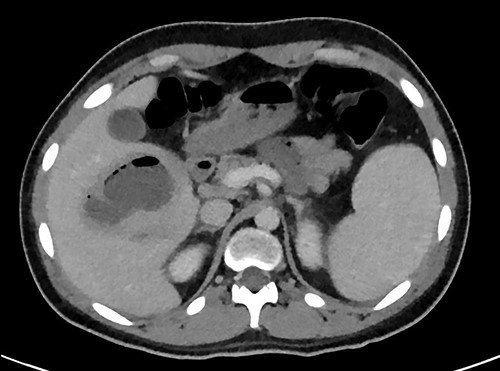

A full lab panel was ordered and revealed a total bilirubin of 1.1, direct bilirubin 0.5, lactate dehydrogenase 196, alkaline phosphatase 80, aspartate transaminase 46 and alanine transaminase 58. A computed tomography (CT) angiographic scan of the chest, abdomen and pelvis revealed the presence of a rim enhancing fluid collection in hepatic segment V with internal gas and containing a metallic foreign body, measuring 8 × 5 cm and consistent with abscess formation (Figs 2–4). The linear tract of the bullet in the right iliac crest was visualized in the CT as well.

Coronal plane of CT showing the retained bullet and hepatic abscess.